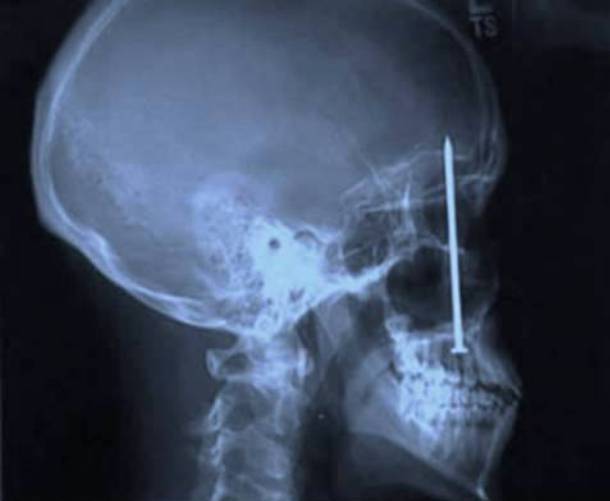

24. A Very Sharp Headache

You'd think you would remember the time when you got a nail stuck in your head - literally piercing right through your skull. But apparently not. This guy went to the doctors complaining of headaches and much to everybody's surprise they found this...Advertisement